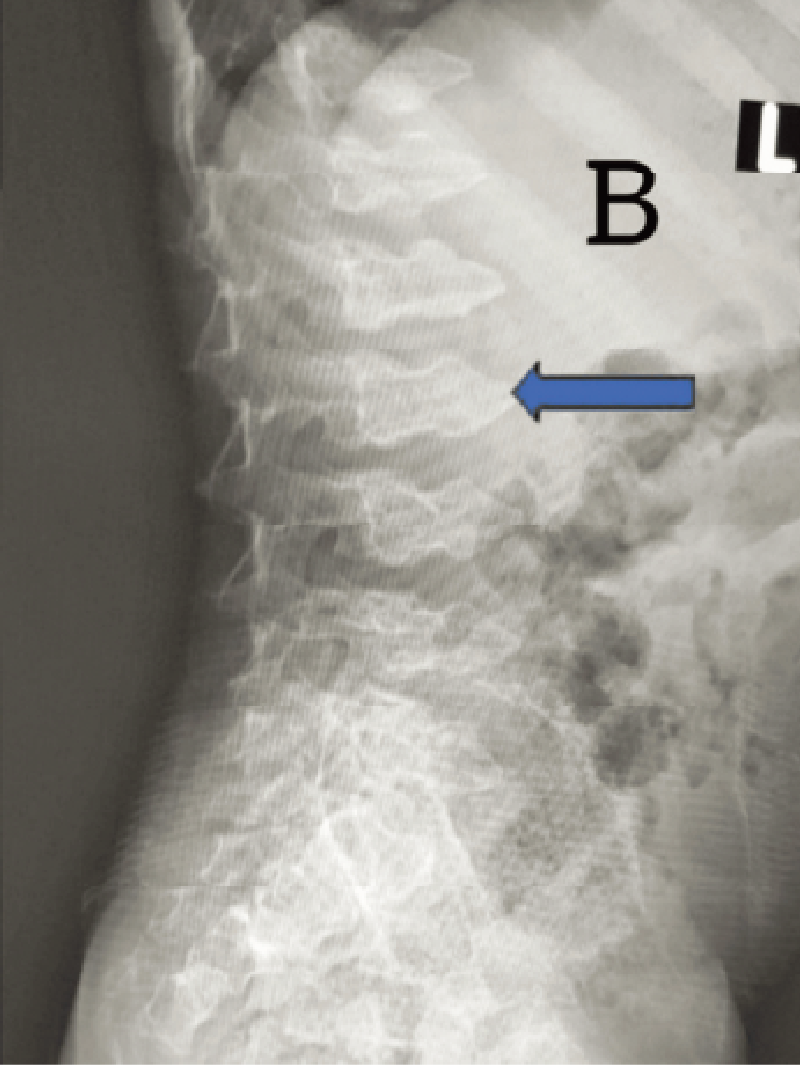

C. 脊椎側面像(2歳、女):椎体前縁が後縁より高い扁平椎が乳幼児期には特徴的である。